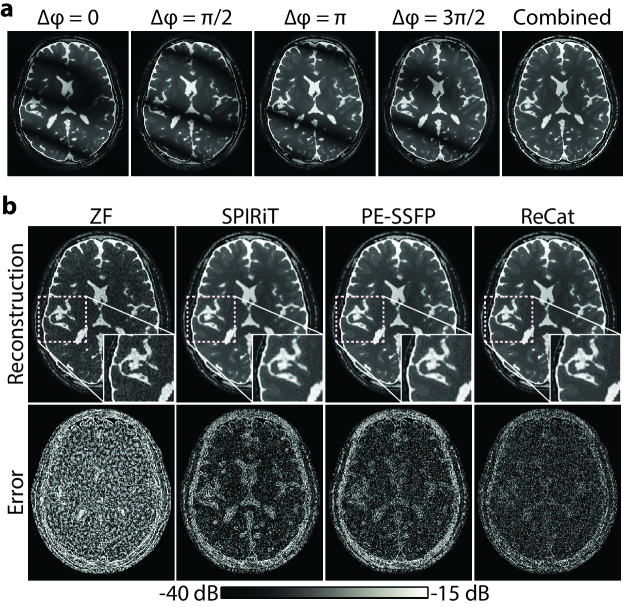

ReCat was first demonstrated on bSSFP acquisitions of a numerical brain phantom with D=8. ZF, SPIRiT, PE-SSFP and ReCat reconstructions and error maps are shown in Fig. 3. Error maps for varying acceleration factors R= are shown in Fig. 4. SPIRiT that independently processes separate acquisitions and PE-SSFP that independently processes separate coils suffer from broad errors at high-spatial frequencies. In comparison, ReCat achieves visibly reduced reconstruction error and enhanced tissue depiction, particularly for R4.

Quantitative assessments regarding ReCat and alternative reconstructions are listed in Table 1 for N=2-8 and R=4-16. ReCat yields higher PSNR values compared to SPIRiT and PE-SSFP at all N and R, except for two cases R=4, N=8 and R=4, N=4 where the techniques perform similarly. On average, ReCat improves PSNR by 2.01.0 dB over SPIRiT, and by 2.00.5 dB over PE-SSFP (meanstd across subjects; average for N=2-8, R=8-16).